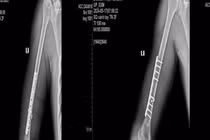

ThS.BSNT Đặng Văn Hiếu – khoa Phẫu thuật chấn thương chỉnh hình và Y học thể thao, Bệnh viện E cho biết, nam thanh niên nhập viện trong tình trạng bị biến dạng cánh tay và hạn chế vận động khuỷu tay phải. Kết quả chụp X-quang cho thấy người bệnh bị gãy 1/3 dưới xương cánh tay phải. Đây là tổn thương nghiêm trọng, có nguy cơ ảnh hưởng lâu dài đến chức năng tay phải nếu không được điều trị kịp thời.

Sau khi đánh giá toàn diện, các bác sĩ quyết định thực hiện phương pháp phẫu thuật kết hợp xương bằng nẹp vít. Đây là kỹ thuật hiện đại và phổ biến trong điều trị gãy xương cánh tay, mang lại hiệu quả cao giúp người bệnh gãy xương mau lành, cố định vững chắc vị trí gãy và tạo điều kiện thuận lợi cho quá trình liền xương.